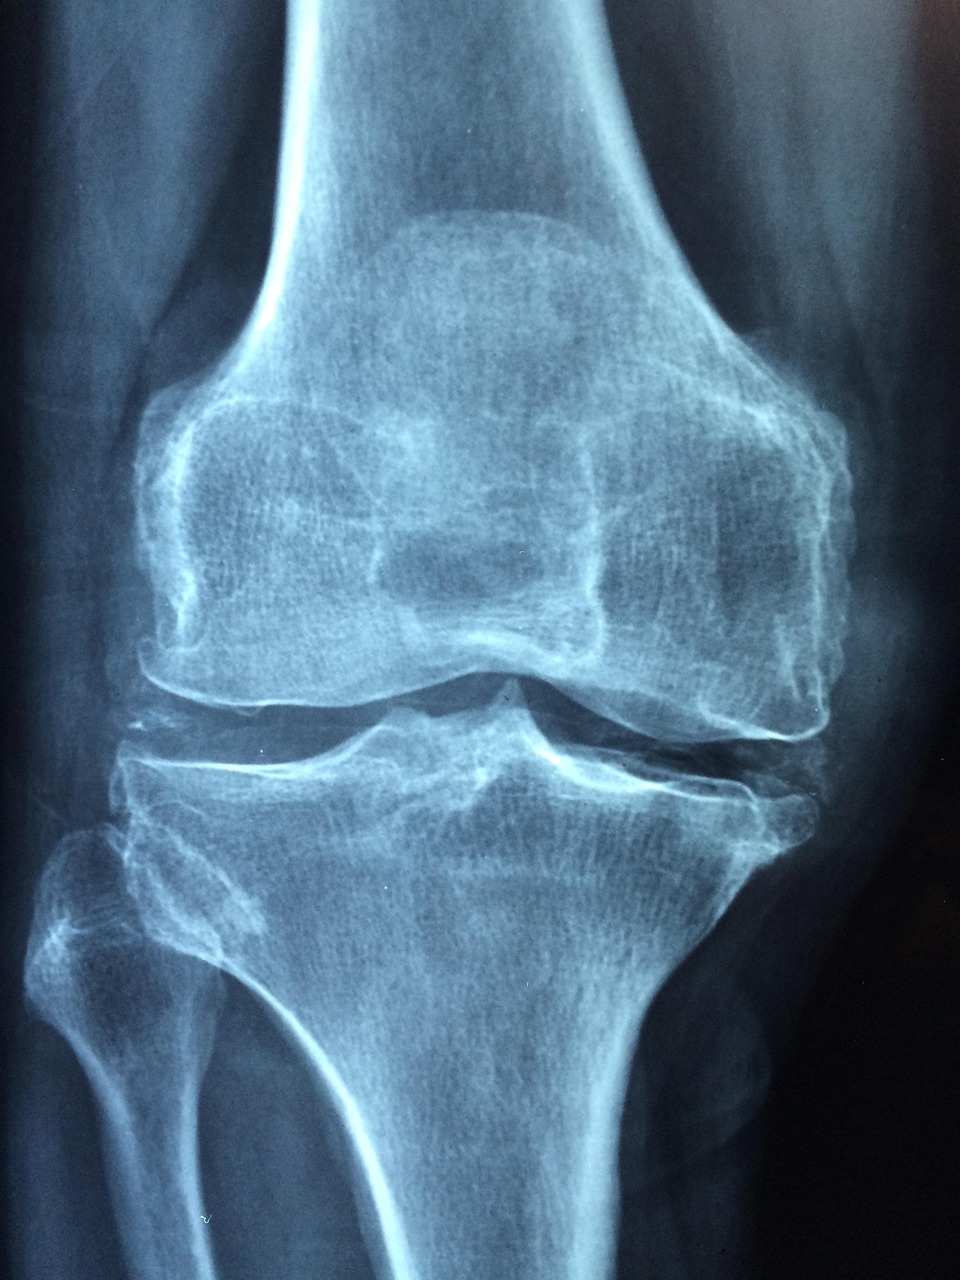

1. 골다공증이란 무엇인가?

골다공증은 뼈의 강도가 약해져 작은 충격에도 골절이 쉽게 일어나는 만성 질환입니다. 뼈의 내부가 구멍이 숭숭 뚫린 듯한 상태가 되어, 넘어지거나 가벼운 충격에도 손목, 척추, 대퇴골 골절이 발생할 수 있습니다.

2. 골다공증 검사가 중요한 이유

골다공증은 초기에는 자각 증상 없이 진행되다가 골절이 발생하고 나서야 발견되는 경우가 많습니다. 특히 여성은 폐경 이후 5~10년간 골밀도가 급격히 감소하기 때문에 정기적인 검사가 필수입니다.